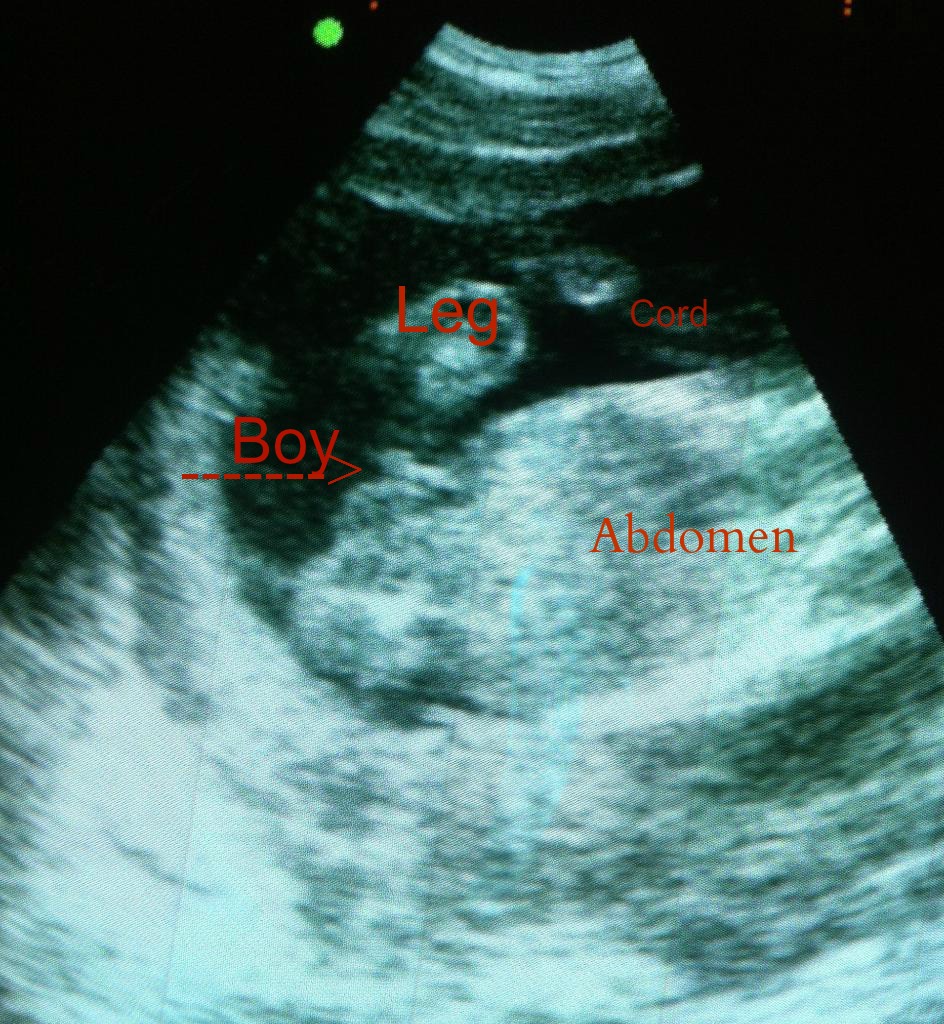

The first shot is hard to tell if that is cord or boy parts, but the second looks very boyish to me. What are your thoughts? This is 16 weeks.

Ok I edited the one photo to try to illustrate what I am seeing. Obviously this isn't a great angle for gender determination, but I thought I would try it out.

I think that's a very clear boy nub! It's angled upwards.